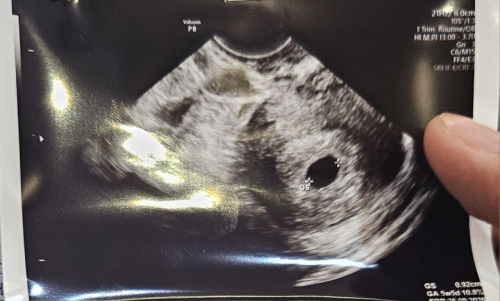

Hallo kak.. Boleh minta sarannya nggaa? Jadi aku hamil TM 1 baru mau 2 bulan Suami tetep geger minta HB Sedangkan harus di kurangi dlu kan ya.. Karena aku dlu juga punya riwayat keguguran Dan di kehamilan yg ini, aku gampang mual juga Bingung bun.. Harus gimanaa Sarannya dong bun😪#mohonbantujawabbunda